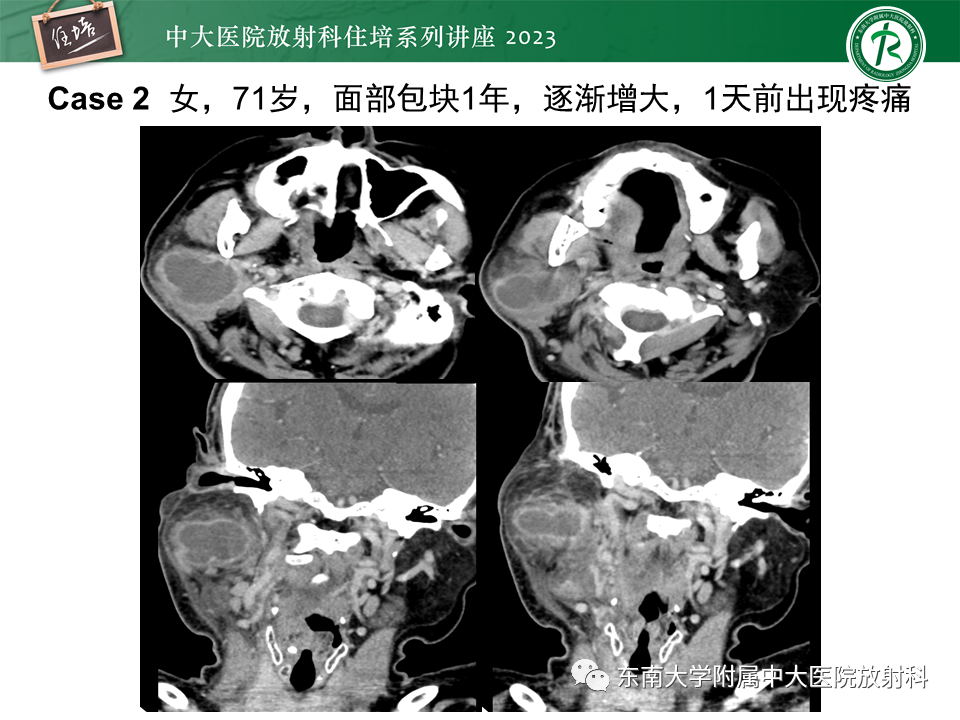

腮腺病变影像表现及诊断思路